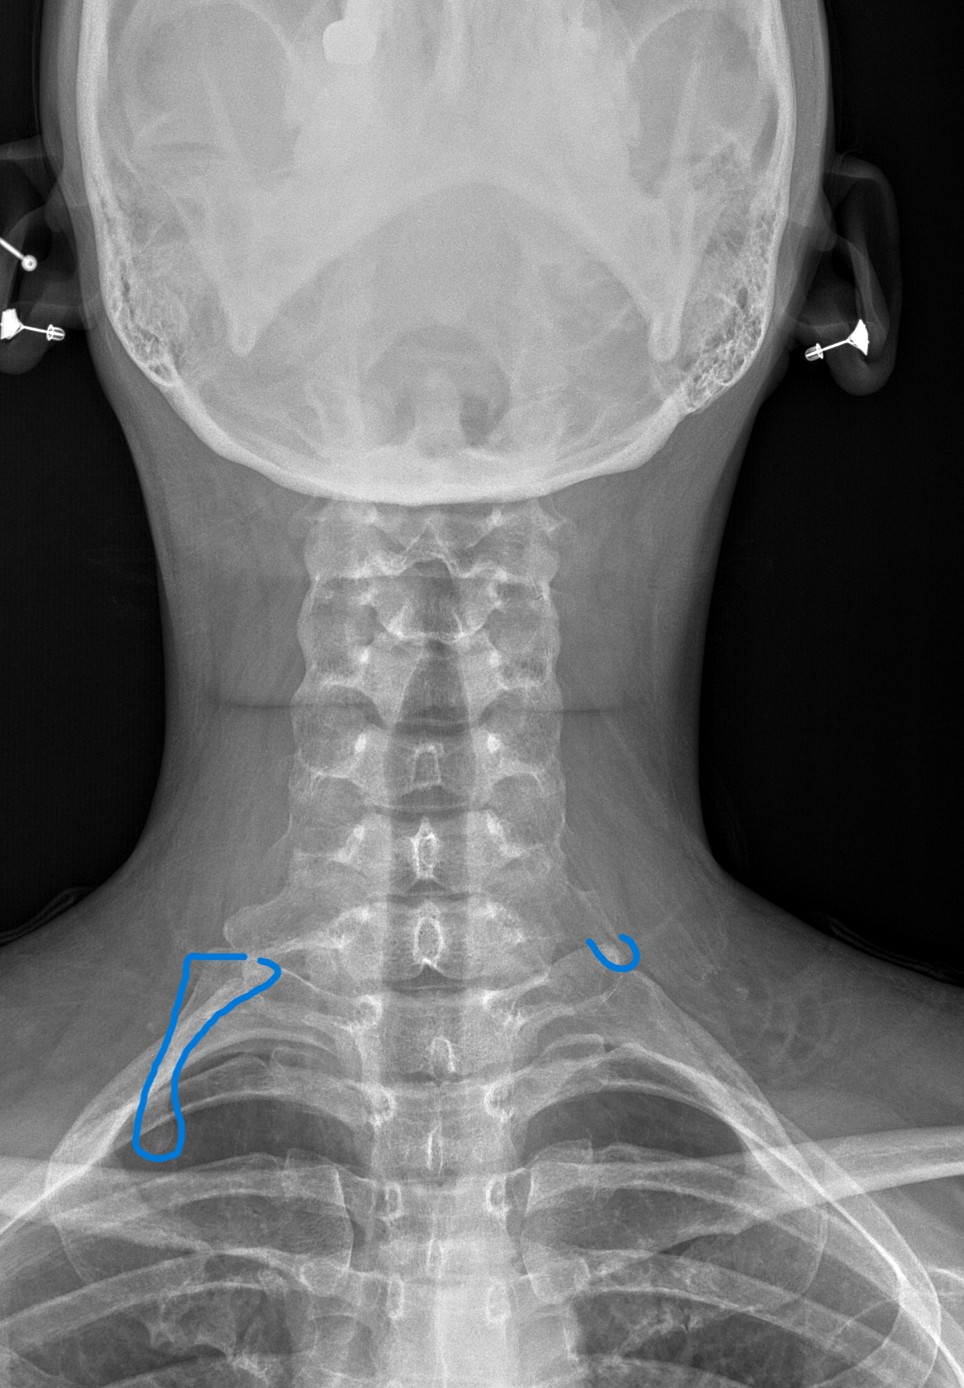

DACBRs Diagnose a Chronic Clavicle Fracture

DACBRs Diagnose a Chronic Clavicle Fracture Fig. 1 AP cervical view Fig. 2 AP cervical view showing red annotation highlights